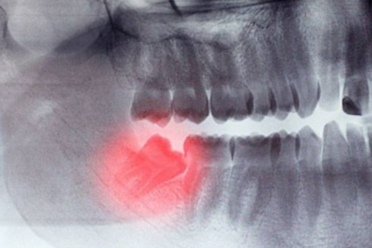

Мы умеем и любим удалять сложные 8-е зубы и делаем это максимально быстро! Да-да те самые восьмерки, с которыми наши некоторые коллеги не хотят связываться и отправляют пациентов в отделение ЧЛХ или куда-то еще. Если удаление 8-го зуба заняло у нас более 30 минут, то мы сделали его вам в подарок!